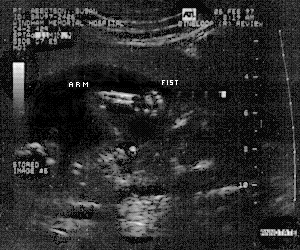

And take a peek at our newest member. A Humu in vitro! #1#2#3#4

As of July 17th, she's a Humu ex-vitro.